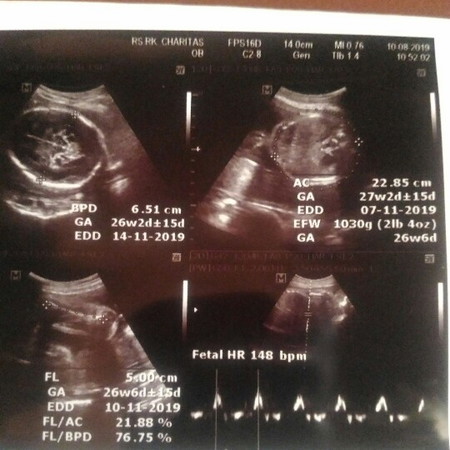

Setelah bulan lalu nangis bombay dan cemas sangat karena kontraksi dan hrs dirawat bedress total, alhamdulillah bulan ini kata dokter sehat. Semoga kita sehat trs ya syg sampe lahiran